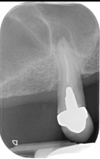

7

Q

what other radiographs other than periapicals can be used to assess periapical inflamm pathology?